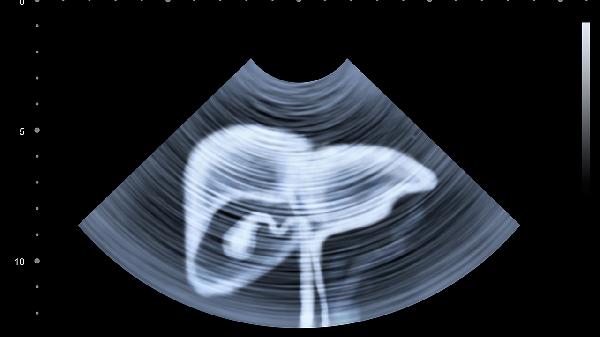

肝癌患者超声检查的五大特征主要有肝内占位性病变、低回声或混合回声团块、边缘不规则、后方回声增强、血流信号异常。肝癌是肝脏常见的恶性肿瘤,早期发现和治疗对预后有重要影响,超声检查是肝癌筛查和诊断的重要手段之一。

肝癌在超声检查中最常见的表现是肝内出现占位性病变。这类病变通常表现为肝脏内局部异常回声区域,与周围正常肝组织形成明显对比。占位性病变可能单发或多发,大小不等,形态各异。超声检查可以清晰显示病变的位置、大小和数量,为后续诊断和治疗提供重要依据。肝内占位性病变的出现往往提示肝脏存在肿瘤性改变,需结合其他检查进一步明确性质。

肝癌在超声图像上多表现为低回声或混合回声团块。低回声团块是指病变区域回声强度低于周围正常肝组织,这可能与肿瘤组织密度和结构改变有关。混合回声团块则表现为高低回声混杂,常见于肿瘤内部存在坏死、出血或钙化等情况。回声特征的变化有助于判断肿瘤的病理类型和生长特点,对临床诊断和治疗方案选择具有指导意义。

肝癌病灶在超声图像上常呈现边缘不规则的特征。这种不规则可能表现为分叶状、毛刺状或模糊不清的边界,反映了肿瘤浸润性生长的特点。边缘不规则的程度与肿瘤恶性程度相关,边界越不规则,恶性可能性越高。超声检查可以清晰显示病灶边缘特征,帮助医生评估肿瘤的生物学行为和侵袭性,为临床分期和治疗决策提供参考。

部分肝癌病灶在超声检查中会出现后方回声增强现象。这是由于肿瘤组织与正常肝组织声阻抗差异导致的声学效应,表现为病灶后方回声强度高于周围组织。后方回声增强多见于囊实性肿瘤或肿瘤内部存在液化坏死区域。这一特征有助于鉴别诊断,但需注意与其他肝脏囊性病变相区分,结合其他影像学检查综合判断。

肝癌病灶在彩色多普勒超声检查中常表现为血流信号异常。肿瘤组织因新生血管形成和血流动力学改变,可呈现丰富血流信号、杂乱血流分布或高速血流频谱。血流信号异常程度与肿瘤恶性程度和生长活性相关,高血供肿瘤往往提示更具侵袭性。超声造影检查可以更清晰地显示肿瘤微循环特征,提高肝癌诊断的准确性。